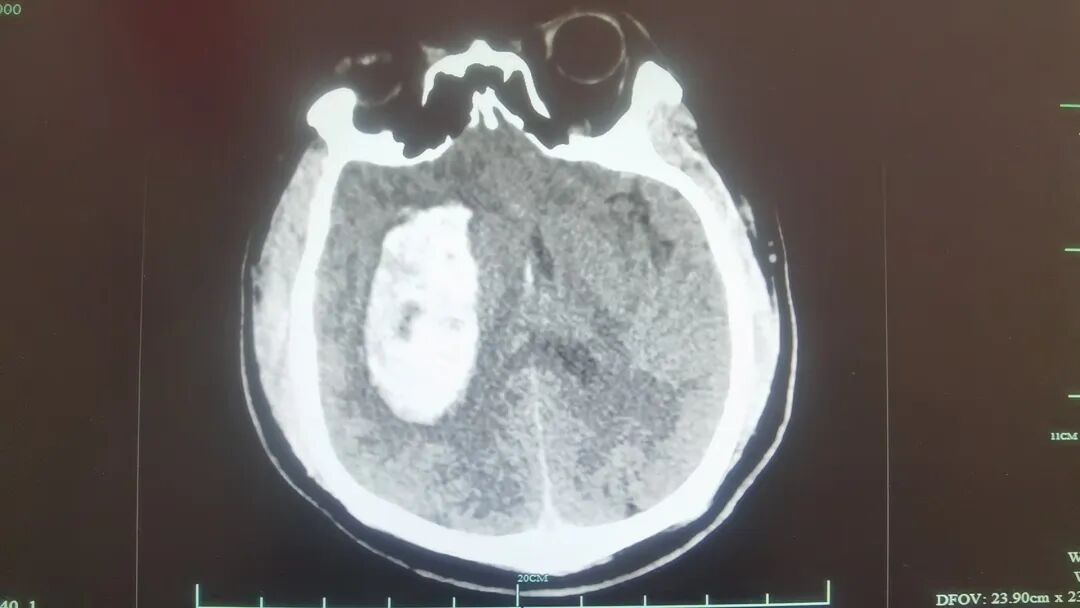

急诊头颈动脉CTA检查提示,动脉粥样硬化改变,右侧颈内动脉C6段中度狭窄,右侧基底节区脑出血。脑外科医护团队立即为高先生进行手术,清除血肿,降低颅内压。术后,高先生生命体征逐渐平稳,被转入ICU接受加强监护与治疗。

我院急诊科副主任卢军锋表示,血压是血液在血管内流动时所产生的压力,我们正常血压不超过140/90mmHg。高先生来到医院时有创血压监测高达360/183mmHg,属于极度危险的状态。